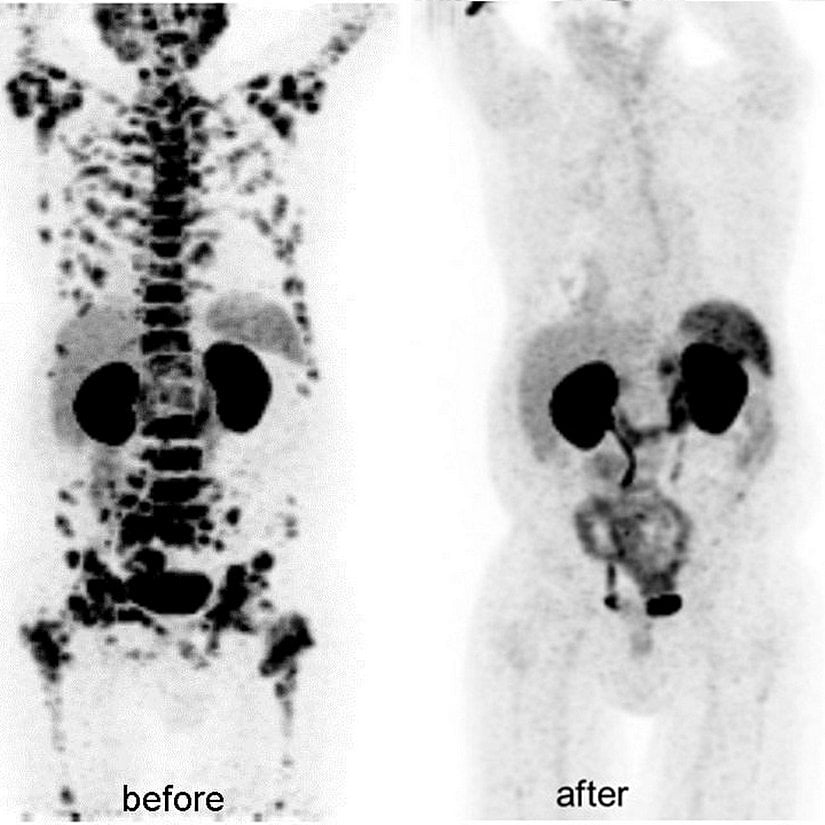

Kanser hücreleri, normal hücrelere göre daha yüksek metabolik aktiviteler gösterir. İşleyişlerindeki bu farklılıktan dolayı kanserli dokular, PET taramalarında parlak bölgeler halinde görünür. Bu sayede PET taraması kanser teşhisi dışında şu amaçlara da hizmet eder:

- Kanserin yayılımının izlenmesi

- Kanser tedavisinin etkinliğinin ölçümü

- Tekrarlamış kanserlerin tespiti